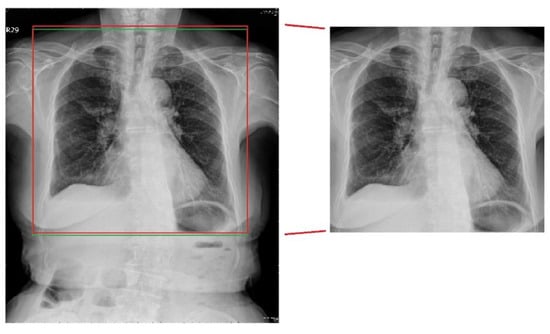

4.1.2. Traditional Lung-Segmentation Results

The results of the traditional lung-area segmentation method at each stage of the operations are depicted in Figure 8. In the last lung boundary identification stage, the red frame indicates the detected area, while the green frame shows the ground truth area for comparison. As can be seen, while the traditional method successfully identified the general lung area, it failed to capture the finer details at the lung boundary, resulting in slight misalignment with the ground truth area.

Figure 8.

Traditional segmentation result.